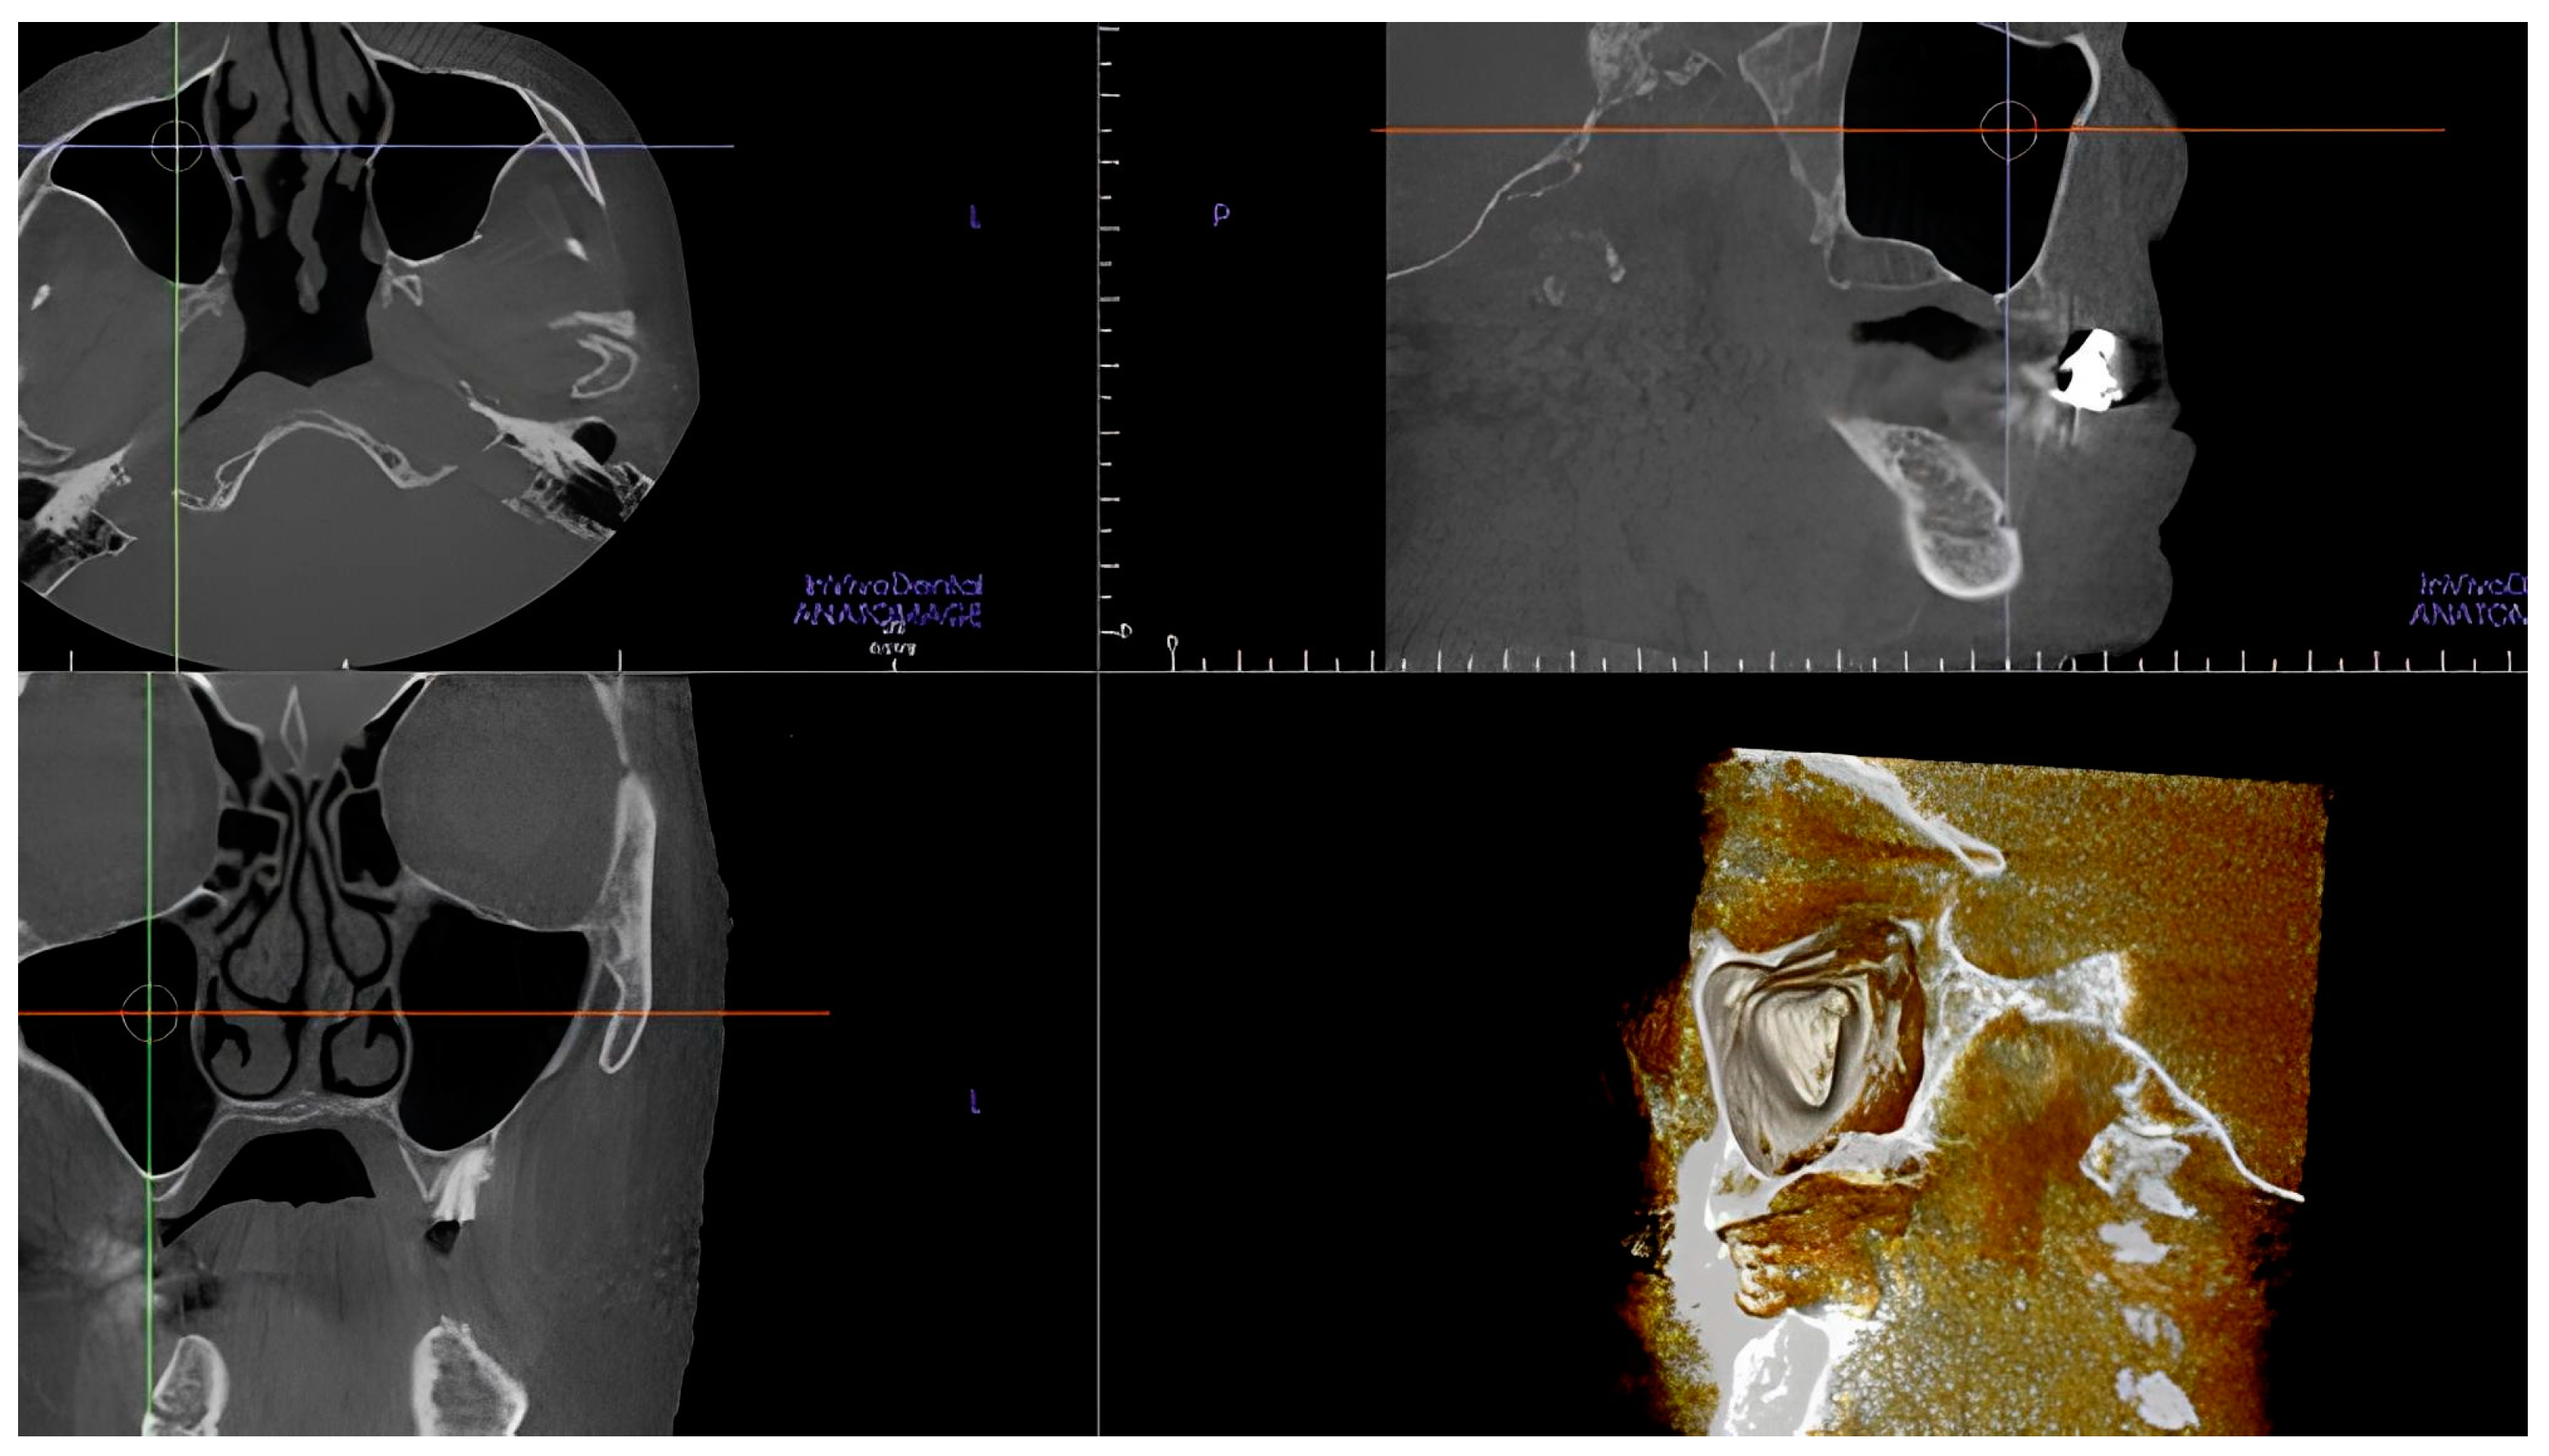

- The length of the arterial pathway in the mesiodistal dimension, on cross-section setting at 1 mm (Figure 2);

- The height of the maxillary bone crest in the cranio-caudal direction, on cross-section at the level of the first superior molar (Figure 3);

- The presence of the septa on cross-section (Figure 4);

- The height of the septa on cross-section setting from 2 mm to 0 mm, to better evaluate the maxillary sinus: this was measured from the apex of the septa to its bottom on the basal bone;